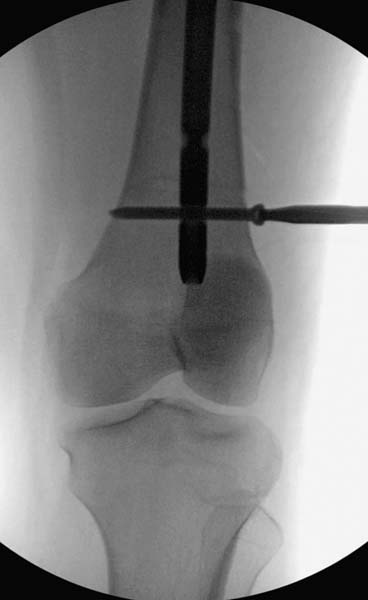

> стабильная.. На третьий день провели стабилизацию перелома бедра

> антеградным остеосинтезом.

> Закрытый БИОС решает множественные проблемы связанные с лечением

> переломов, но проблема дистальной блокировки без рентгена до сих пор

> остается нерешенной. Рекламированные производителями приспособления для

> дистальной блокировки из-за различной кривизны кости не эффективны или

> стоит очень дорого (Smith&Nephew SureLock). Задержка операции из-за

> блокировки не всегда удовлетворяет, и многих вынуждает искать

> альтернативные методы фиксации. С результатами таких действий,

> остеомиелитом и несращениями, встречаемся в ежедневной жизни..

> Для решения проблемы дистальной блокировки компания DigiMed недавно

> предложила систему блокировки без рентгена. Пока в стране только два набора

> и только для антеградных гвоздей, но компания работает над созданием

> устроиства для других гвоздей тоже..

> Результат первых случаев показала отсутствие разницы между занятиями на

> муляжах, а также Workshop и с удивительной точностью вывел латерально над

> кожей специальное сверло. Дальше по сверлу тонкий направитель и проводится

> сверление каннюлированным сверлом....